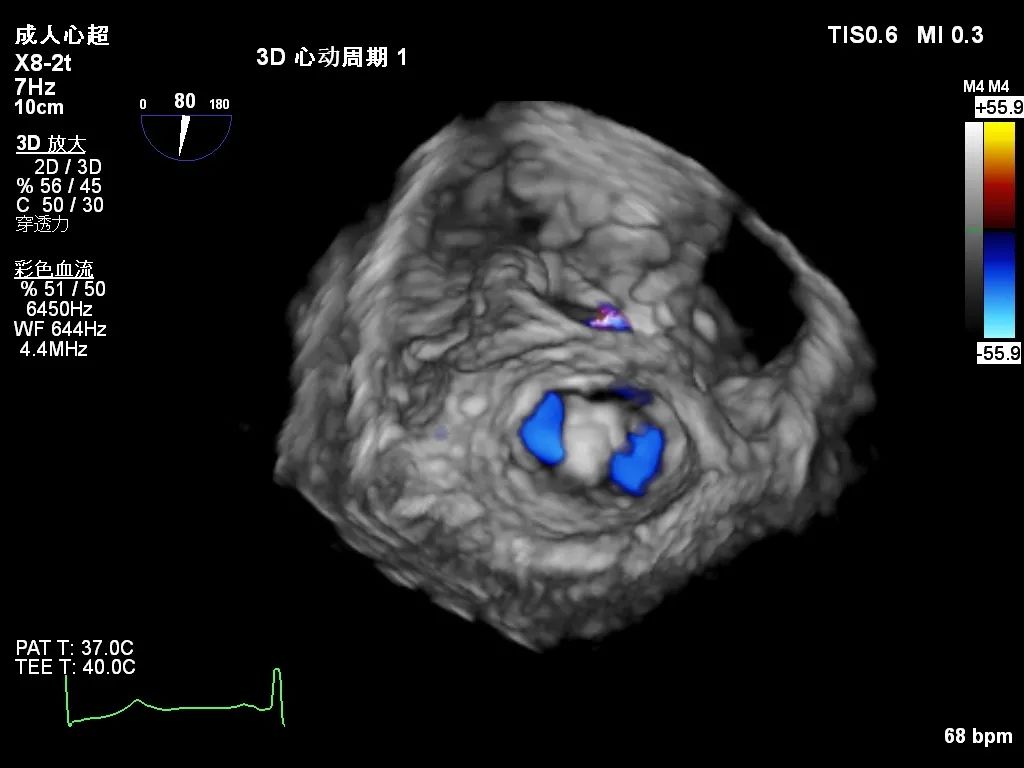

术后超声心动图

患者在麻醉科团队保驾护航下,器械经股静脉穿刺房间隔,通过输送系统送入左心房,到达二尖瓣瓣膜反流处,在经食道超声心动图及DSA引导下,术者通过反复评估二尖瓣膜脱垂范围、抓捕位置、反流程度之后,进行精准夹合,成功植入DragonFly瓣膜夹1枚。术后超声即刻患者反流降低至轻度,二尖瓣跨瓣平均压差未超过4mmHg,左房压下降,肺静脉逆流减轻,血流动力学改善明显,手术取得圆满成功。